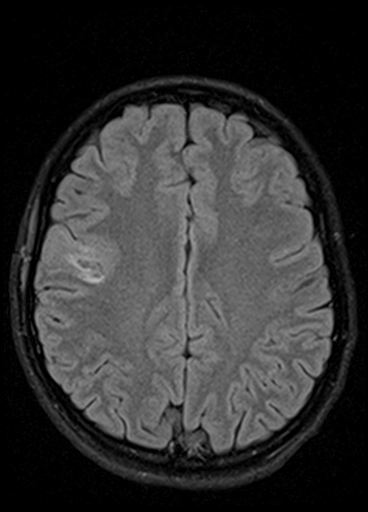

«Например, недавно в отделение поступил подросток с постепенно нарастающей очаговой неврологической симптоматикой. По результатам МРТ головного мозга была выявлена опухоль в функциональнозначимой зоне головного мозга (отвечающей за движение в конечностях) и без отчетливых границ с мозговой тканью. Открытое удаление новообразования могло привести к инвалидизации девочки, однако для определения дальнейшей тактики лечения требовался гистологический анализ патологической ткани с целью исключения злокачественного характера бластоматозного процесса. Было решено провести стереотаксическую биопсию с использованием нейронавигационной станции. Для проведения предварительных расчетов безопасной траектории прохождения биопсионной иглы до зоны-мишени (центральной части опухоли) в навигационную станцию были загружены данные МРТ обследования пациентки, затем в режиме реального времени были привязаны внешние анатомические ориентиры головы и лица. После компьютерной обработки полученных данных весь ход операции можно было контролировать на мониторе навигационной станции в трехмерном режиме. При помощи специальной биопсийной иглы были взяты образцы патологической ткани в намеченной зоне (что было подтверждено при контрольной МРТ)», — рассказывает заведующий отделением нейрохирургии для детей №7 к.м.н. Александр Вонгиевич Ким.

Визуализация введения иглы во время стереотаксической биопсии

Пациентка перенесла операцию удовлетворительно, осложнений в постоперационном периоде не было. Гистологический анализ подтвердил наличие опухоли, она оказалась доброкачественной, поэтому девочке не было показано онкостатическое лечение. Было лишь рекомендовано проходить регулярный МРТ контроль.

| МРТ до операции | МРТ после операции (1-е сутки после операции) | |